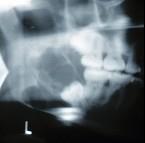

问题 某患者一侧下颌磨牙区、下颌角及升支部渐进性膨大,按之有乒乓球感。X线片(如图)示多房性密度减低影,分房大小相差悬珠,分隔清晰锐利、阴影边缘呈切迹状,阴影内牙根尖有不规则吸收。该病最可能的诊断是 ( )

选项 A.颌骨血管瘤 B.成骨肉瘤 C.牙源性纤维瘤 D.牙源性角化囊肿 E.成釉细胞瘤

答案 E